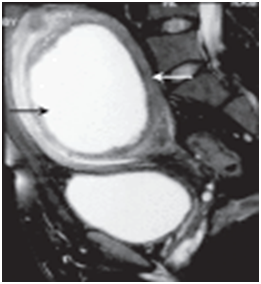

The place of MRI in the pre-operative diagnosis cannot be overemphasized.14–16 The images below from MRI using T1 T2 weighted views delineate the origin of cystic mass better than other imaging techniques and should be well applied were appropriate in the preoperative management of patient’s with massive cystic swelling of the abdomen. The cost implication and inaccessibility of this tool limits the use in routine gynaecological practice (Figure 5) (Figure 6).